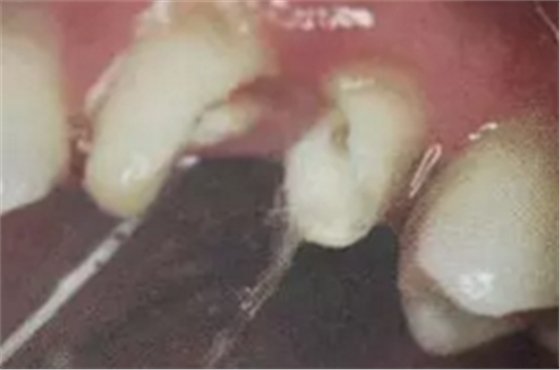

2. 清除根管壁殘留物

根管壁殘留物的存在直接影響纖維樁的粘接和固位,這也是導(dǎo)致纖維樁脫落的主要原因。

(根管內(nèi)殘留物)

個(gè)人見解:必要的情況下先開闊根管口建立一定的視角后,慢速手機(jī)上G鉆為引導(dǎo)鉆,由號(hào)遞增引導(dǎo)開闊通路;P鉆預(yù)備樁道,同樣需要由小向大號(hào)遞增,直到選擇好適合的號(hào)預(yù)備到規(guī)定測(cè)量的深度即可,再配合纖維樁系統(tǒng)中各型號(hào)纖維樁所匹配的樁道鉆,預(yù)備、修整成與纖維樁相適應(yīng)的樁道。

預(yù)備后根管壁上會(huì)不同程度的牙膠和封閉劑等殘留物,所以樁道預(yù)備前后建議X線片輔助檢查預(yù)備深度等情況,而殘留物也會(huì)很清晰地顯現(xiàn)。

根管銼去除殘留物,很難去除干凈,而備取樁道時(shí),禁止使用牙膠溶解劑(如:丁克除、氯仿)等有機(jī)溶劑去除殘留物,以防破壞根尖區(qū)牙膠的封閉和防止附著根管壁影響粘接。

(超聲去除根管殘留物)

通常此時(shí)以超聲潔牙機(jī)更換較細(xì)工作尖進(jìn)入根管(根管消毒沖洗液配合清潔工作后面會(huì)提到),徹底去除樁道根管壁上的附著殘留物,效果明顯。再配合X線片、根管顯微鏡輔助檢查清理的情況下更佳。